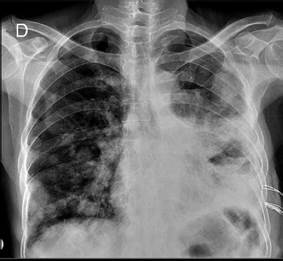

Se realizó radiografía simple de tórax que mostró imágenes compatibles con el signo de “suelta de globos” en todos los campos pulmonares, junto con derrame pleural izquierdo (Figura 1).

FIGURA Nro.1: Placa de rayos x de tórax que evidencia signo suelta de globos, de balas de cañón o signo de escopetazo, múltiples nódulos pulmonares bien definidos de distribución bilateral y aleatoria, de diferentes tamaños, es muy sugerente de metástasis pulmonares.

Múltiples nódulos pulmonares bilaterales, de tamaño variable y distribución aleatoria, conforman el signo de suelta de globos o balas de cañón (Figura 1). Este patrón es altamente sugestivo de metástasis pulmonares, principalmente secundarias al carcinoma de células renales (2).